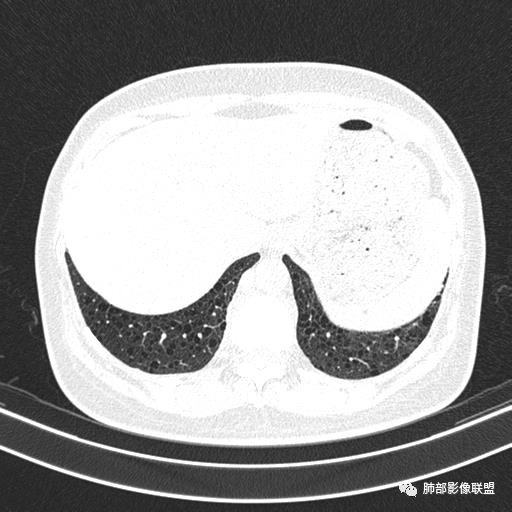

中年女性,不吸烟

双肺弥漫囊腔,累及肋膈角,囊腔形态相对规则单一。

CT平扫示双肺弥漫分布大小不等囊状薄壁透光区,无内、中、外带分布差异,间质稍示增厚。拟LAM

我也支持刘老师。中年女性,咳嗽气喘,有苯吸入史,双肺野多发囊腔,囊腔形态相对规则,大小不一,壁薄,有的似无壁,双肺弥漫磨玻璃影,有间质性改变,育龄期女性,首选考虑lam,但是患者有吸入苯病史半年,囊腔形态不是很规则,大小不一,分布不均匀,有的无壁似小叶中央肺气肿,有弥漫性磨玻璃及间质性改变,不排除吸入引起的间质性肺炎?

中年女性,双肺弥漫性磨玻璃密度影,并见弥漫性分布大小不一囊腔,壁薄,形态规则,考虑lam,鉴别苯中毒肺损伤致间质改变

中年女性育龄期妇女,咳嗽气喘,无吸烟史,有苯吸入史。影像:双肺弥漫均匀小囊腔,无明显分布优势,囊腔形态欠规则,壁薄,部分囊腔边缘血管征,伴双肺弥漫磨玻璃影,无结节,考虑lam,鉴别苯中毒肺损伤,囊腔多有分布优势,小叶中心分布为主,形态规整等

中年女性,两肺弥漫分布囊性低密度影,壁薄,相对规则,境界尚清晰,考虑LAM

中年育龄期女性,双肺多发含气囊腔弥漫性分布,囊间肺组织结构正常,常规考虑Lam

女,46,活动性气喘1年。苯吸入史半年。胸部CT:两肺弥漫囊腔,上至肺尖,下至肋膈角,形态类似小囊腔。考虑:LAM,鉴别LIP,BHD,PLCH等。

双肺弥漫大小不一薄壁含气囊腔,囊间肺组织正常,正常肺背景,肺尖肺底受累;青年女性,气喘,支持LAM

双肺多发大小相近的囊状影,分布趋势趋于一致,中年女性,考虑LAM。部分囊内见血管及分隔影,小叶中心性肺气肿代排

CT表现:双肺弥漫大小不等的薄壁囊腔,囊壁<2mm,外形规则,血管影多位于囊腔周围,囊腔之间肺组织正常,随着疾病进展到晚期,囊腔变大、增多,不可胜数,囊腔可融合成较大的囊,与肺气肿相似,形成间质性肺纤维化。部分病例可出现结节影。